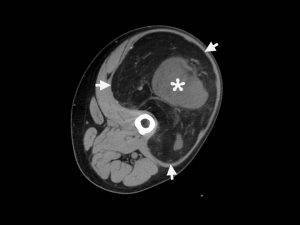

Компьютерная томография (КТ) – сканирование левого бедра. Новообразование выделено стрелками. В центре наблюдается мягкотканный компонент (звездочка).

67-летний мужчина с медленно растущей массой на левой ноге в области паха. Пациент некурящий и не диабетик. Низкий сигнал интенсивности.

Компьютерная томография (КТ) играет важную роль в предоперационной оценке опухоли мягких тканей. Хорошо дифференцированную липосаркому можно отличить от других видов опухолей.